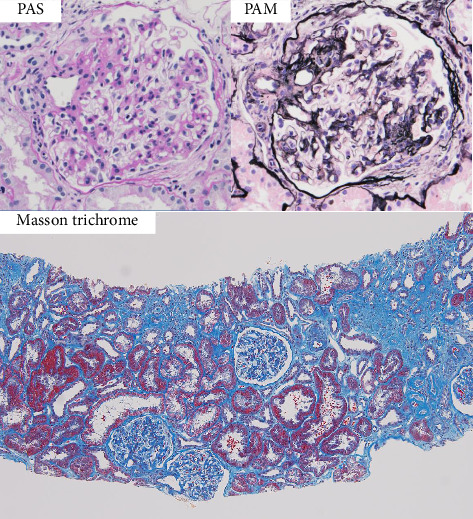

一位63岁的日本家庭主妇因持续3个月的血尿和蛋白尿而入院。在59岁时,她在另一家医院被诊断为神经结节病,并接受口服糖皮质激素治疗1年。血清血管紧张素转换酶(ACE)和1,25 -二羟基维生素D水平升高。计算机断层扫描显示气管分叉淋巴结病变,肺和肝脏弥漫性结节影。肾活检结果与IgA肾病一致,无非干酪化肉芽肿,肾小球半乳糖缺乏IgA1 (Gd-IgA1)在肾小球系膜区染色。由于临床怀疑结节病,肝脏活检显示炎症伴多个非干酪化肉芽肿。诊断为IgA肾病合并结节病。口服强的松龙后,轻度蛋白尿持续存在;然而,血清肌酐水平恢复正常,血尿消失,血清ACE和1,25 -二羟基维生素D水平恢复正常。虽然一些结节病患者偶尔会出现肾小球肾炎,但结节病合并IgA肾病的病例报道很少。这是首例在IgA肾病和结节病患者中发现肾小球Gd-IgA1的病例报告。

A 63-year-old Japanese housewife was admitted to our hospital because of hematuria and proteinuria lasting for 3 months. At the age of 59 years, she was diagnosed with neurosarcoidosis at another hospital, and she received oral glucocorticoid therapy for 1 year. Her serum angiotensin-converting enzyme (ACE) and 1, 25-dihydroxyvitamin D levels were elevated. Computed tomography showed lymphadenopathy of the tracheal bifurcation and diffuse nodular shadow in the lungs and liver. Renal biopsy findings were compatible with IgA nephropathy without noncaseating granulomas and glomerular galactose-deficient IgA1 (Gd-IgA1) was stained in mesangial area. Because of clinical suspicion of sarcoidosis, liver biopsy was also performed, which showed inflammation with multiple noncaseating granulomas. The patient was diagnosed with IgA nephropathy coincident with sarcoidosis. After oral administration of prednisolone, mild proteinuria persisted; however, serum creatinine level was normalized, hematuria disappeared, and serum ACE and 1, 25-dihydroxyvitamin D levels returned to normal. Although some patients with sarcoidosis occasionally present with glomerulonephritis, there have been few case reports of sarcoidosis with IgA nephropathy. This was the first case report in which glomerular Gd-IgA1 was identified in a patient with IgA nephropathy and sarcoidosis.